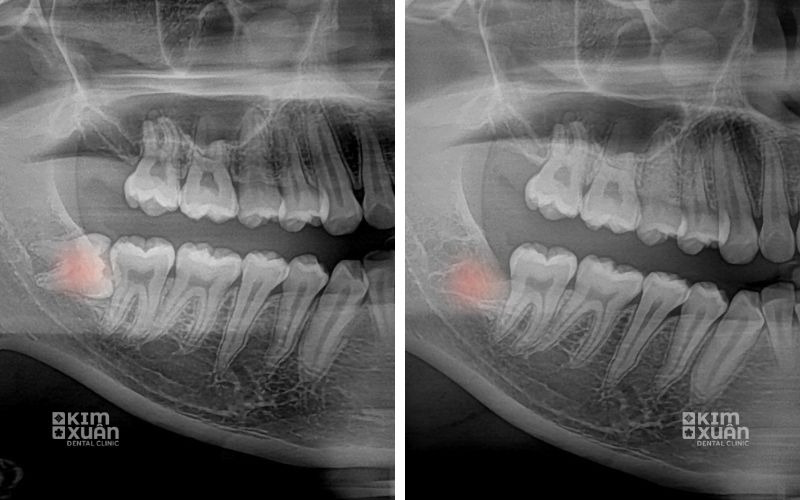

Lây lan sâu răng sang răng số 7 kế cận

Ảnh hưởng đến răng số 7 bên cạnh

Để xác định chính xác chi phí nhổ răng khôn bị sâu, bác sĩ cần thăm khám trực tiếp và chụp phim X-quang nhằm đánh giá vị trí răng, mức độ sâu, tình trạng viêm nhiễm cũng như ảnh hưởng của răng số 8 đến các răng lân cận.

Chụp phim X-quang đánh giá chính xác vị trí và mức độ răng khôn